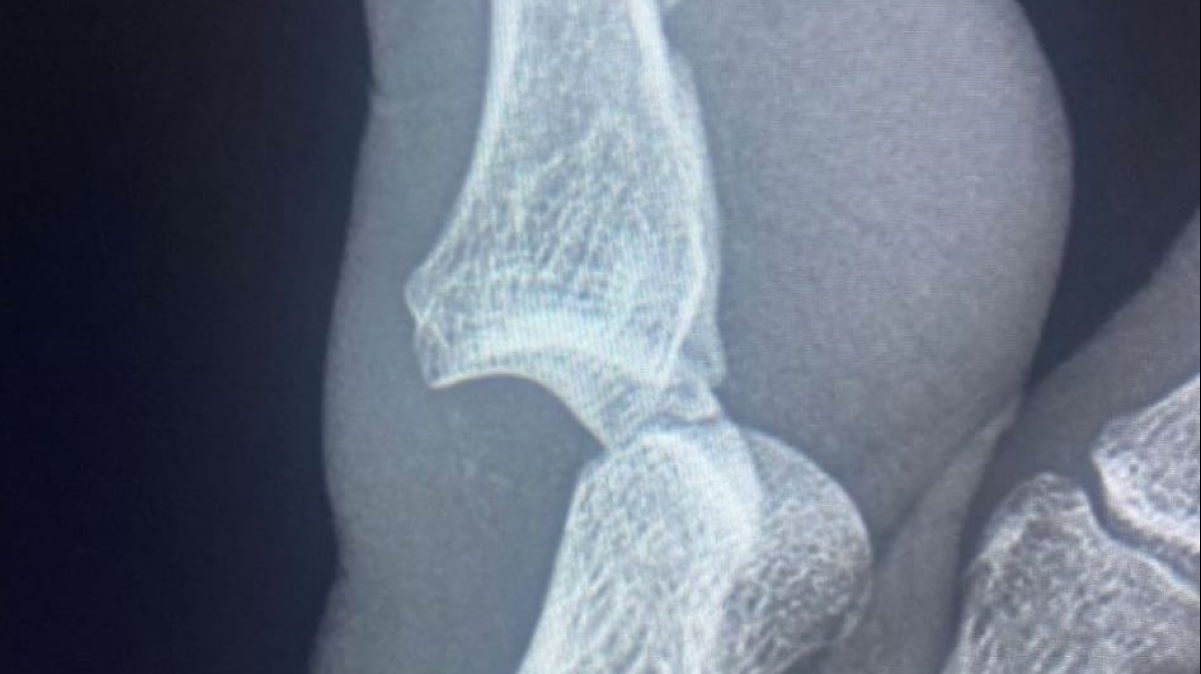

Il francese, via Instagram, ha pubblicato la foto della lastra a cui si è sottoposto dopo il match insieme ad un messaggio: «Ecco com’è finita la duecentesima. Grazie per i vostri messaggi».